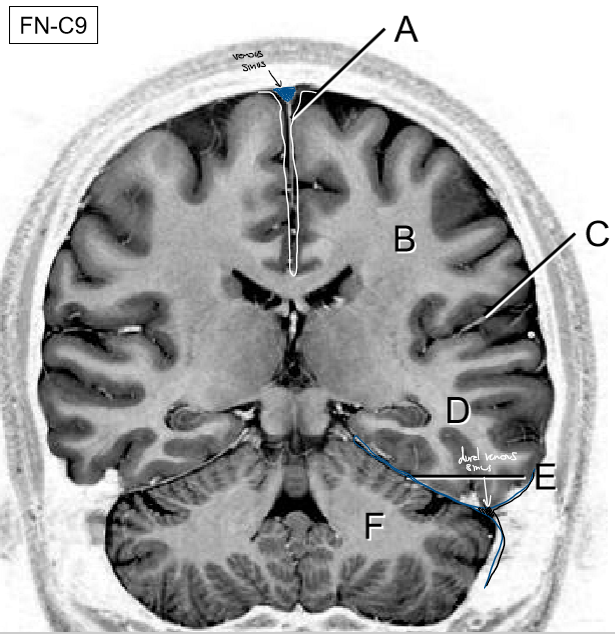

A-F

A: Falx cerebri

B: Parietal lobe

C: Lateral fissure

D: Temporal lobe

E: Tentorium cerebelli

F: Cerebellum

A: Confluence of sinuses

B: Transverse sinus

C: Sigmoid sinus

D: Cavernous sinus

E: Superior petrosal sinus

F: Inferior petrosal sinus